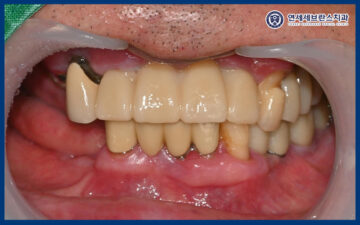

25.07.19

그리고 맞춤형 지대주에 맞는

최종 보철을 제작하여

맞춰보았습니다.

보철물의 형태와 색상,

교합 상태를 꼼꼼하게 확인한 뒤

불편한 부분은 없는지 점검하며

세밀한 조정을 시행하였습니다.